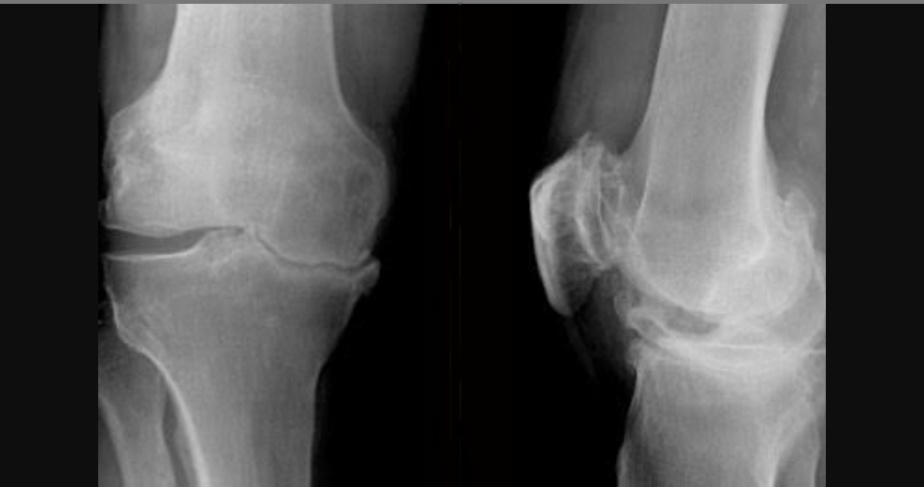

Diacerein-Before treatment

Diacerein-After treatment

X-Ray 2: The anteroposterior and lateral view of the knee joint before and after diacerein treatment

X-ray 2 shows knee joint of osteoarthritis patients before and after treatment with diacerein. Pre-treatment X-ray shows medial intercondylar joint space and femeropatellar joint space narrowing with subchondral sclerosis and osteophyte formation suggestive of severe Osteoarthritic changes. Post-treatment with diacerein shows no significant improvement radiologically.